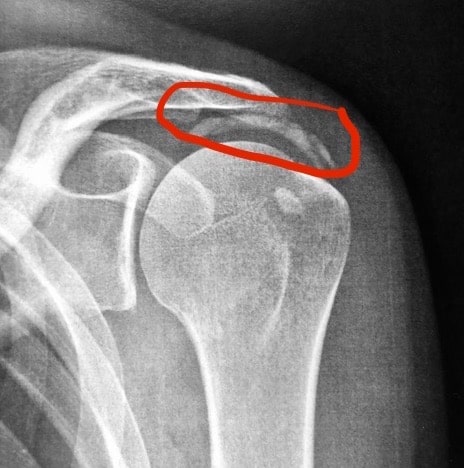

Une radiographie permet de poser le diagnostic, lorsqu’est mis en évidence un pincement et l’apparition de becs osseux (ostéophytes). Ces derniers peuvent avoir pour conséquence une irritation et une usure du tendon de la coiffe des rotateurs. Un kyste synovial peut également apparaître. L’IRM permet de préciser le diagnostic et explore arthrose, bec osseux, kyste et état de la coiffe.

La radiographie de l’épaule met en évidence un pincement de l’interligne articulaire et une production d’os (ostéophytes) autour de la tête de l’humérus, apparaissant comme une goutte.